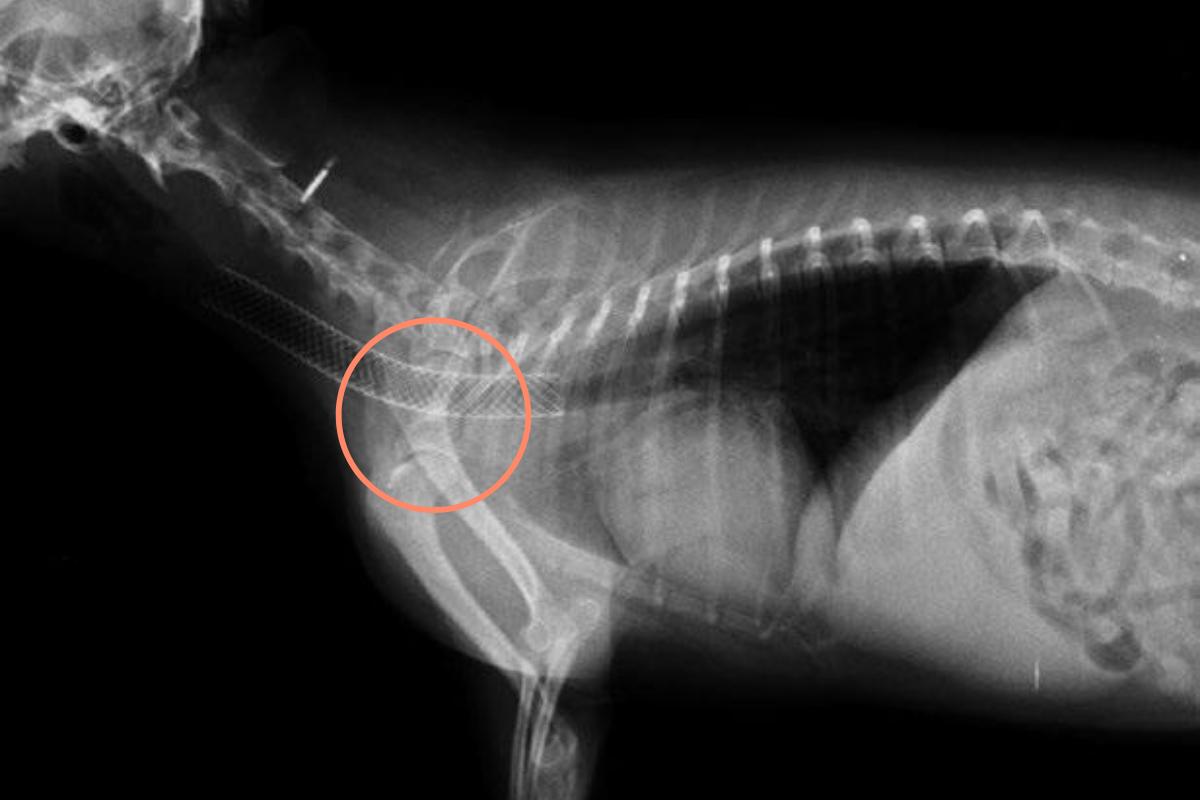

Debido a la disnea más o menos grave que pueden manifestar los gatos con colapso traqueal, las pruebas diagnósticas pueden volverse peligrosas. La mejor prueba diagnóstica para el colapso traqueal es la radiografía. Como el colapso dura tiene un intervalo de tiempo muy breve en la respiración de un gato, se deben tomar radiografías laterales de la tráquea torácica y cervical durante la inspiración y la espiración en un gato no anestesiado y si es posible, una radiografía en movimiento para detectar sí o sí el momento del colapso.

- Colocación de un stent (sonda hueca): dentro de la tráquea para mantenerla abierta.